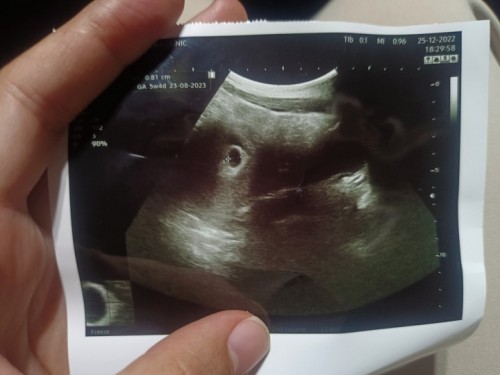

ประจำเดือนมาล่าสุด ประมาณ25ต.ค.65ค่ะ จนถึงวันนี้ 26 ธ.ค. 65 น้องก็น่าจะ 2เดือนแล้ว ก็เลยคิดจะไปฝากครรภ์ค่ะ หมออัลตราซาวด์ออกมาบอกว่ายังไม่มีตัวอ่อนเลย หมอเลยนัด2 สัปดาห์มาตรวจอีกที ส่วนตัวตอนนี้กังวลมากกกกกกก นอนร้องไห้ไปแล้ว กลัวท้องลมมากๆเลย #ท้องลม #ขอคำแนะนำหน่อยค่ะ #ท้องแรกค่ะ

เห็นถุงตั้งครรภ์ไหมค่ะ เรา7สัปดาห์เห็นแค่ถุงตั้งครรภ์ รอไปซาวอีกทีปะมาน10สัปดาห์ค่ะ

จากที่ดูในรูป ถุงตั้งครรภ์กลมสวยนะคะ คิดว่าอีกสองอาทิตย์จะต้องเจอตัวน้องค่ะ

ถุงตั้งครรภ์ยังเล็กมากๆอยู่เลยค่ะ อาจจะตกไข่ช้า รออีก 2-3อาทิตย์ซาวด์ใหม่นะคะ

ในใบซาวน์ 5w4d เองไม่ใช่หรอคะ ถ้า2เดือนคือ8วีค ก็น่าจะเห็นแล้วค่ะ

ถ้าท้องลมถุงน้ำคล้ำจะมีลักษณะเบี้ยวผิดรูปไม่เป็นวงกลมค่ะ